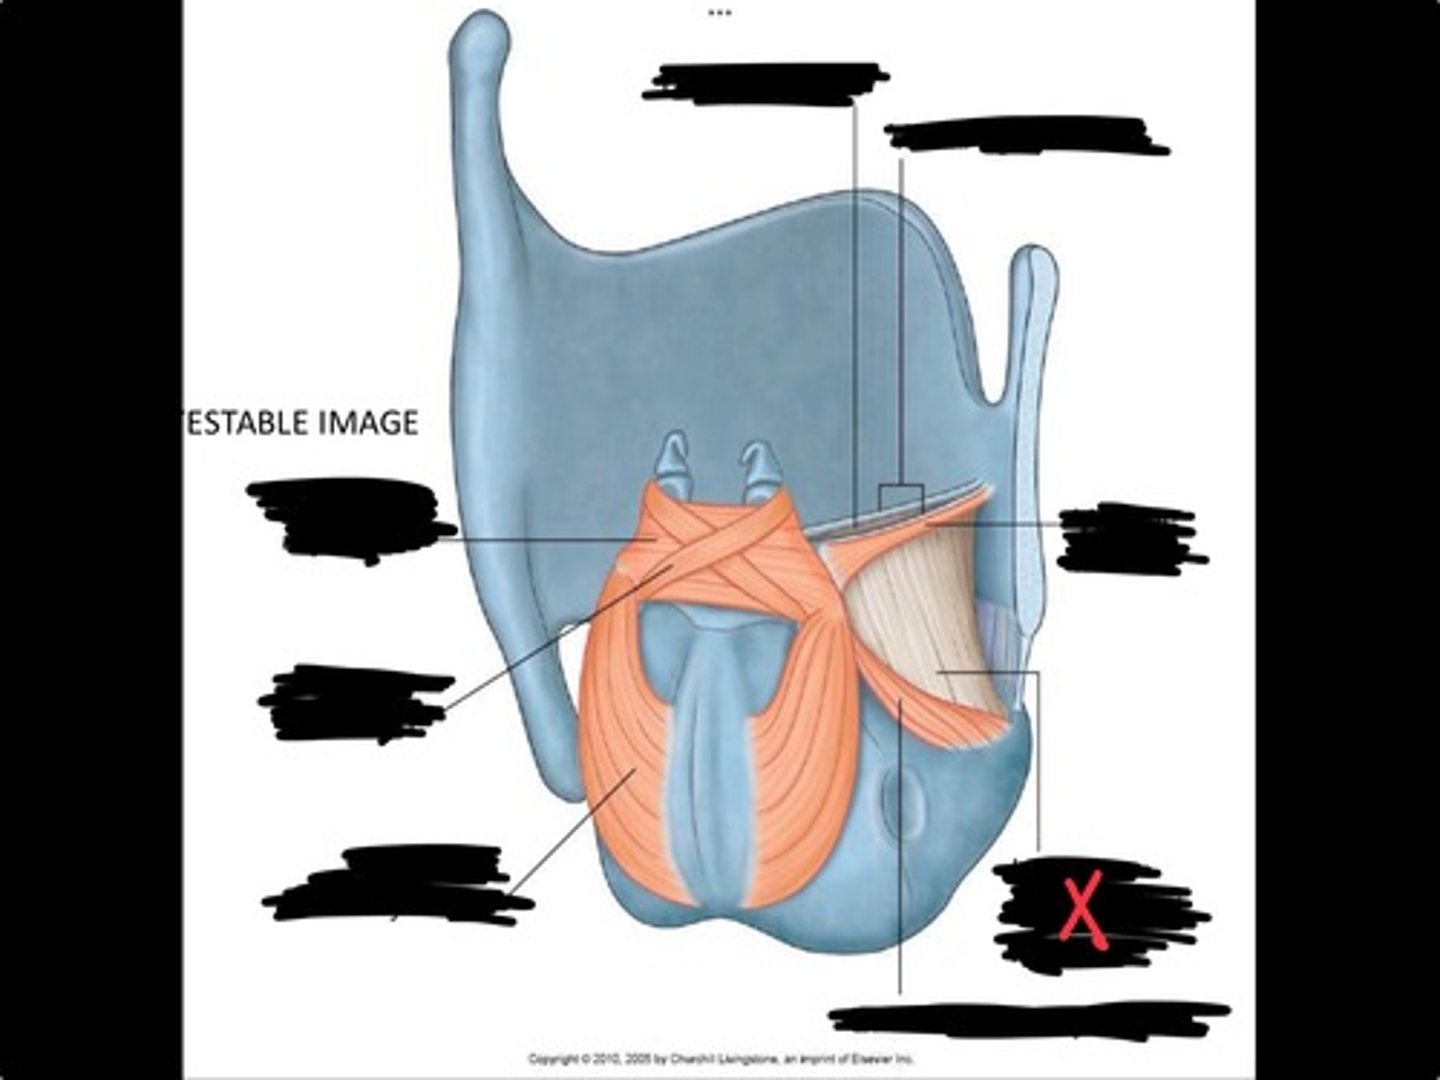

Vocal process of arytenoid

Conus elasticus

Vestibular ligament

Quadrangular membrane

Epiglottis

vocal ligament

Aryepiglottic ligament

Muscular process of arytenoid

Corniculate cartilage

Posterior crico arytenoid

oblique arytenoid

transverse artyenoid

Rima glottidis

Vocal ligament

Vocalis muscle

Lateral cricothyroid ligament

Lateral cricoartenoid